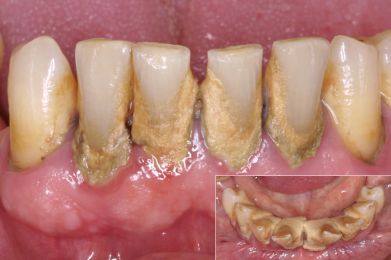

- Ungepflegte Zähne / ggf. Mundgeruch

- Defekte oder braune, schwarze Stellen an den Zähnen, Kronen oder Brücken / Verweigerung von Essen wegen Heiß-/Kaltempfindlichkeit oder Empfindlichkeit süß-sauer / „Fährt rein!“

- Scharfe Kanten an den Zähnen / Verletzungen an Zunge oder Schleimhäuten fallen auf oder werden beklagt / Ständiges Spielen der Zunge an den Zähnen

- Gerötetes oder "zurückgegangenes" Zahnfleisch / Essen hängt ständig zwischen den Zähnen

- Zahnfleisch sieht entzündet (gerötet) aus / ggf. fällt Mundgeruch auf